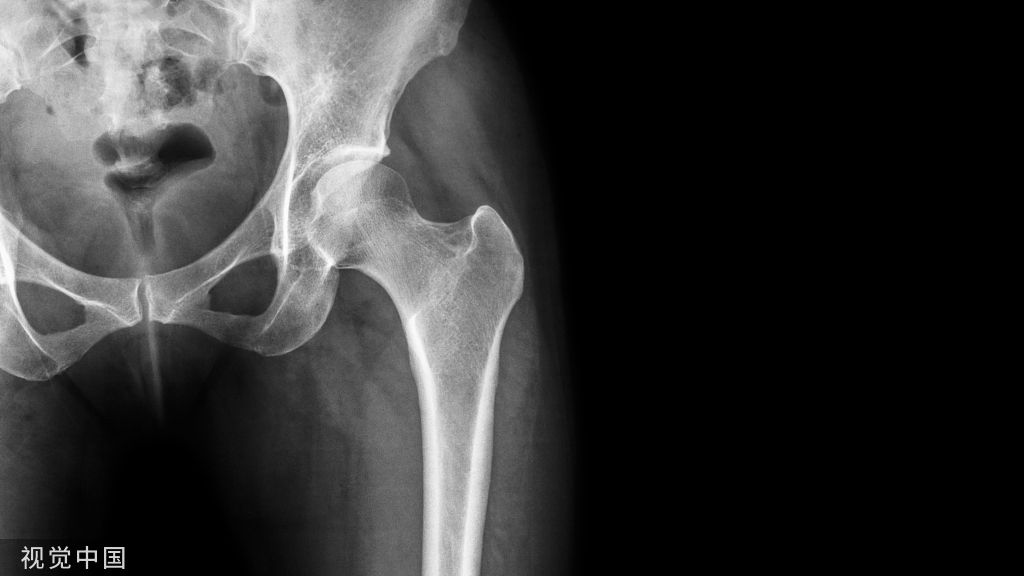

扁平足又叫做足弓塌陷,是指足内侧纵弓平坦,负重力线不正常,出现疲乏或疼痛症状的足扁平畸形,常伴患后足外翻。

小贴士:足弓可以称作是「天然减震器」,它具有很好的弹性,可以减小地面作用于身体的冲击力。